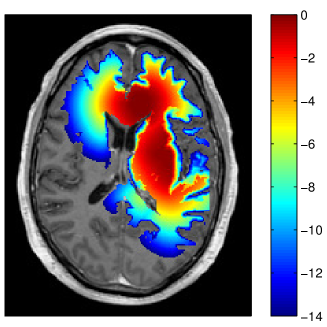

Refer to caption

Figure 3: Simulated tumor cell density based on the segmentation in figure 2 for parameters λw=4.2subscript𝜆𝑤4.2\lambda_{w}=4.2 mm and Dw/Dg=100subscript𝐷𝑤subscript𝐷𝑔100D_{w}/D_{g}=100 (a) and Dw/Dg=10subscript𝐷𝑤subscript𝐷𝑔10D_{w}/D_{g}=10 (b) . The color scale refers to the log10𝑙𝑜subscript𝑔10log_{10} cell density normalized to the carrying capacity.

In this paper, we are concerned with the spatial definition of the target volume as an isoline of the tumor cell density. In that context, the exact value of the infiltration length λwsubscript𝜆𝑤\lambda_{w} is irrelevant because it does not affect the shape of the isolines. Only the abolute values of the tumor cell density associated with the isolines are determined by λwsubscript𝜆𝑤\lambda_{w} 333The value of λwsubscript𝜆𝑤\lambda_{w} will be crucial for dose prescription considered in the accompanying paper [16].. Thus, the only relevant model parameter for this paper is the ratio Dw/Dgsubscript𝐷𝑤subscript𝐷𝑔D_{w}/D_{g}, which determines the shape of the isolines of the cell density together with the brain segmentation. The literature consistently suggests that tumor cells infiltrate gray matter much less than white matter444This holds for the most common case of astrocytomas, not necessarily for oligodentrogliomas (see [12] for a review of glioma growth patterns). This suggests a large value for Dw/Dg1much-greater-thansubscript𝐷𝑤subscript𝐷𝑔1D_{w}/D_{g}\gg 1. Most illustrations in this paper were obtained for Dw/Dg=100subscript𝐷𝑤subscript𝐷𝑔100D_{w}/D_{g}=100. The most appropriate value is however uncertain and we discuss the impact of uncertainties in Dw/Dgsubscript𝐷𝑤subscript𝐷𝑔D_{w}/D_{g} in section 3.5.

In addition to the segmentation, the ratio of white and gray matter diffusion coefficient Dw/Dgsubscript𝐷𝑤subscript𝐷𝑔D_{w}/D_{g} influences the shape of the isolines of the tumor cell density. For Dg=0subscript𝐷𝑔0D_{g}=0, gray matter represents a hard boundary and tumor cells only spread in white matter. For Dw/Dg=1subscript𝐷𝑤subscript𝐷𝑔1D_{w}/D_{g}=1, tumor cells spread equally in white and gray matter and the shape of the target is solely influenced by anatomical constraints. In figure 3 the simulated tumor cell density is compared for Dw/Dg=10subscript𝐷𝑤subscript𝐷𝑔10D_{w}/D_{g}=10 and Dw/Dg=100subscript𝐷𝑤subscript𝐷𝑔100D_{w}/D_{g}=100. For smaller Dw/Dgsubscript𝐷𝑤subscript𝐷𝑔D_{w}/D_{g}, the cell density is more washed out (figure 3b) compared to a larger Dw/Dgsubscript𝐷𝑤subscript𝐷𝑔D_{w}/D_{g} where the tumor cell density follows more closely the white matter structure (figure 3a). It has been discussed above that the cortical gray matter has a thickness of only a few millimeters. As a consequence, varying Dw/Dgsubscript𝐷𝑤subscript𝐷𝑔D_{w}/D_{g} has little impact on the global shape of the target volume. The most significant changes for this patient are around the lateral sulcus.